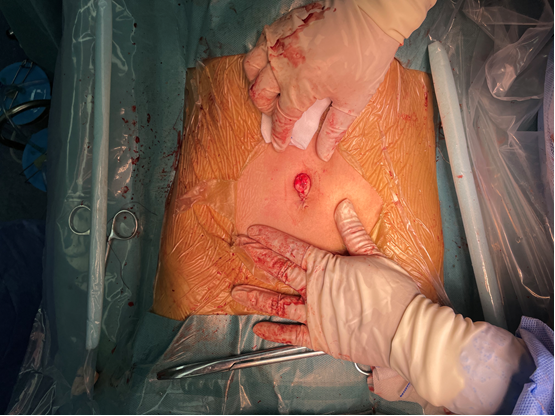

丁文清主任利用单孔腹腔镜为**女士进行手术

术中间断吸引出囊液约3500ml